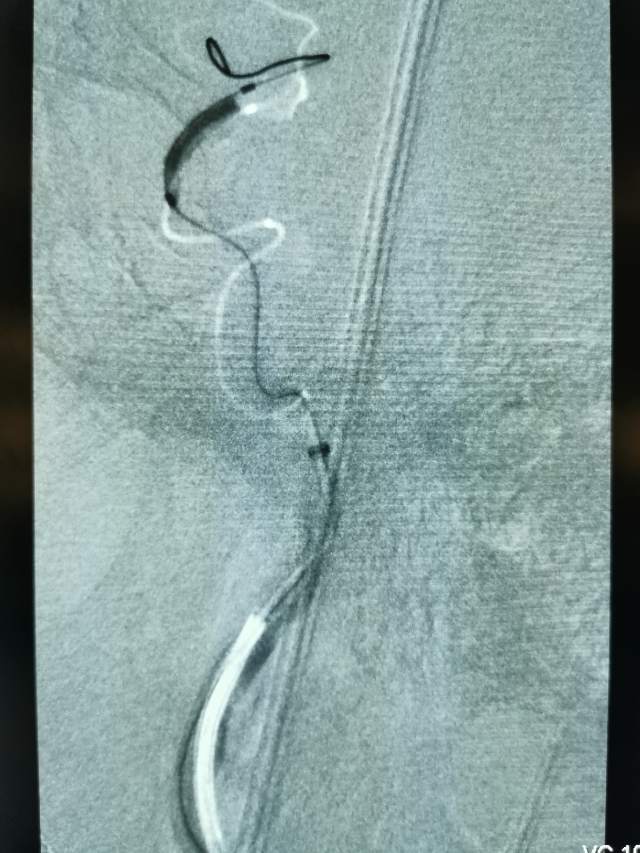

今日,我们重新为患者开通闭塞的血管,术后,患者重新焕发勃勃生机,俨然换了一个人~~~

一个月后根据复查情况酌情给予二期支架植入